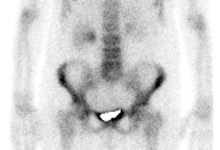

Nuclear medicine bone scan

After injecting a radioactively marked phosphate complex into a vein, the patient should wait at least two hours until enough activity has accumulated in the bones, in order to record it with a gamma camera. During this time, the patient should drink at least one bottle of water, in order to make the maximum possible radioactive material that has not accumulated in the bones excrete through the kidneys. Shortly before the beginning of the examination the patient will be once again sent to the toilet to empty his bladder. The scintigraphic images are mostly taken in the supine position, whereas the gamma camera is moving along the whole body, first of all, from the front and then from behind. If necessary, additional SPECT images will be taken with the gamma camera rotating around definite parts of the body.